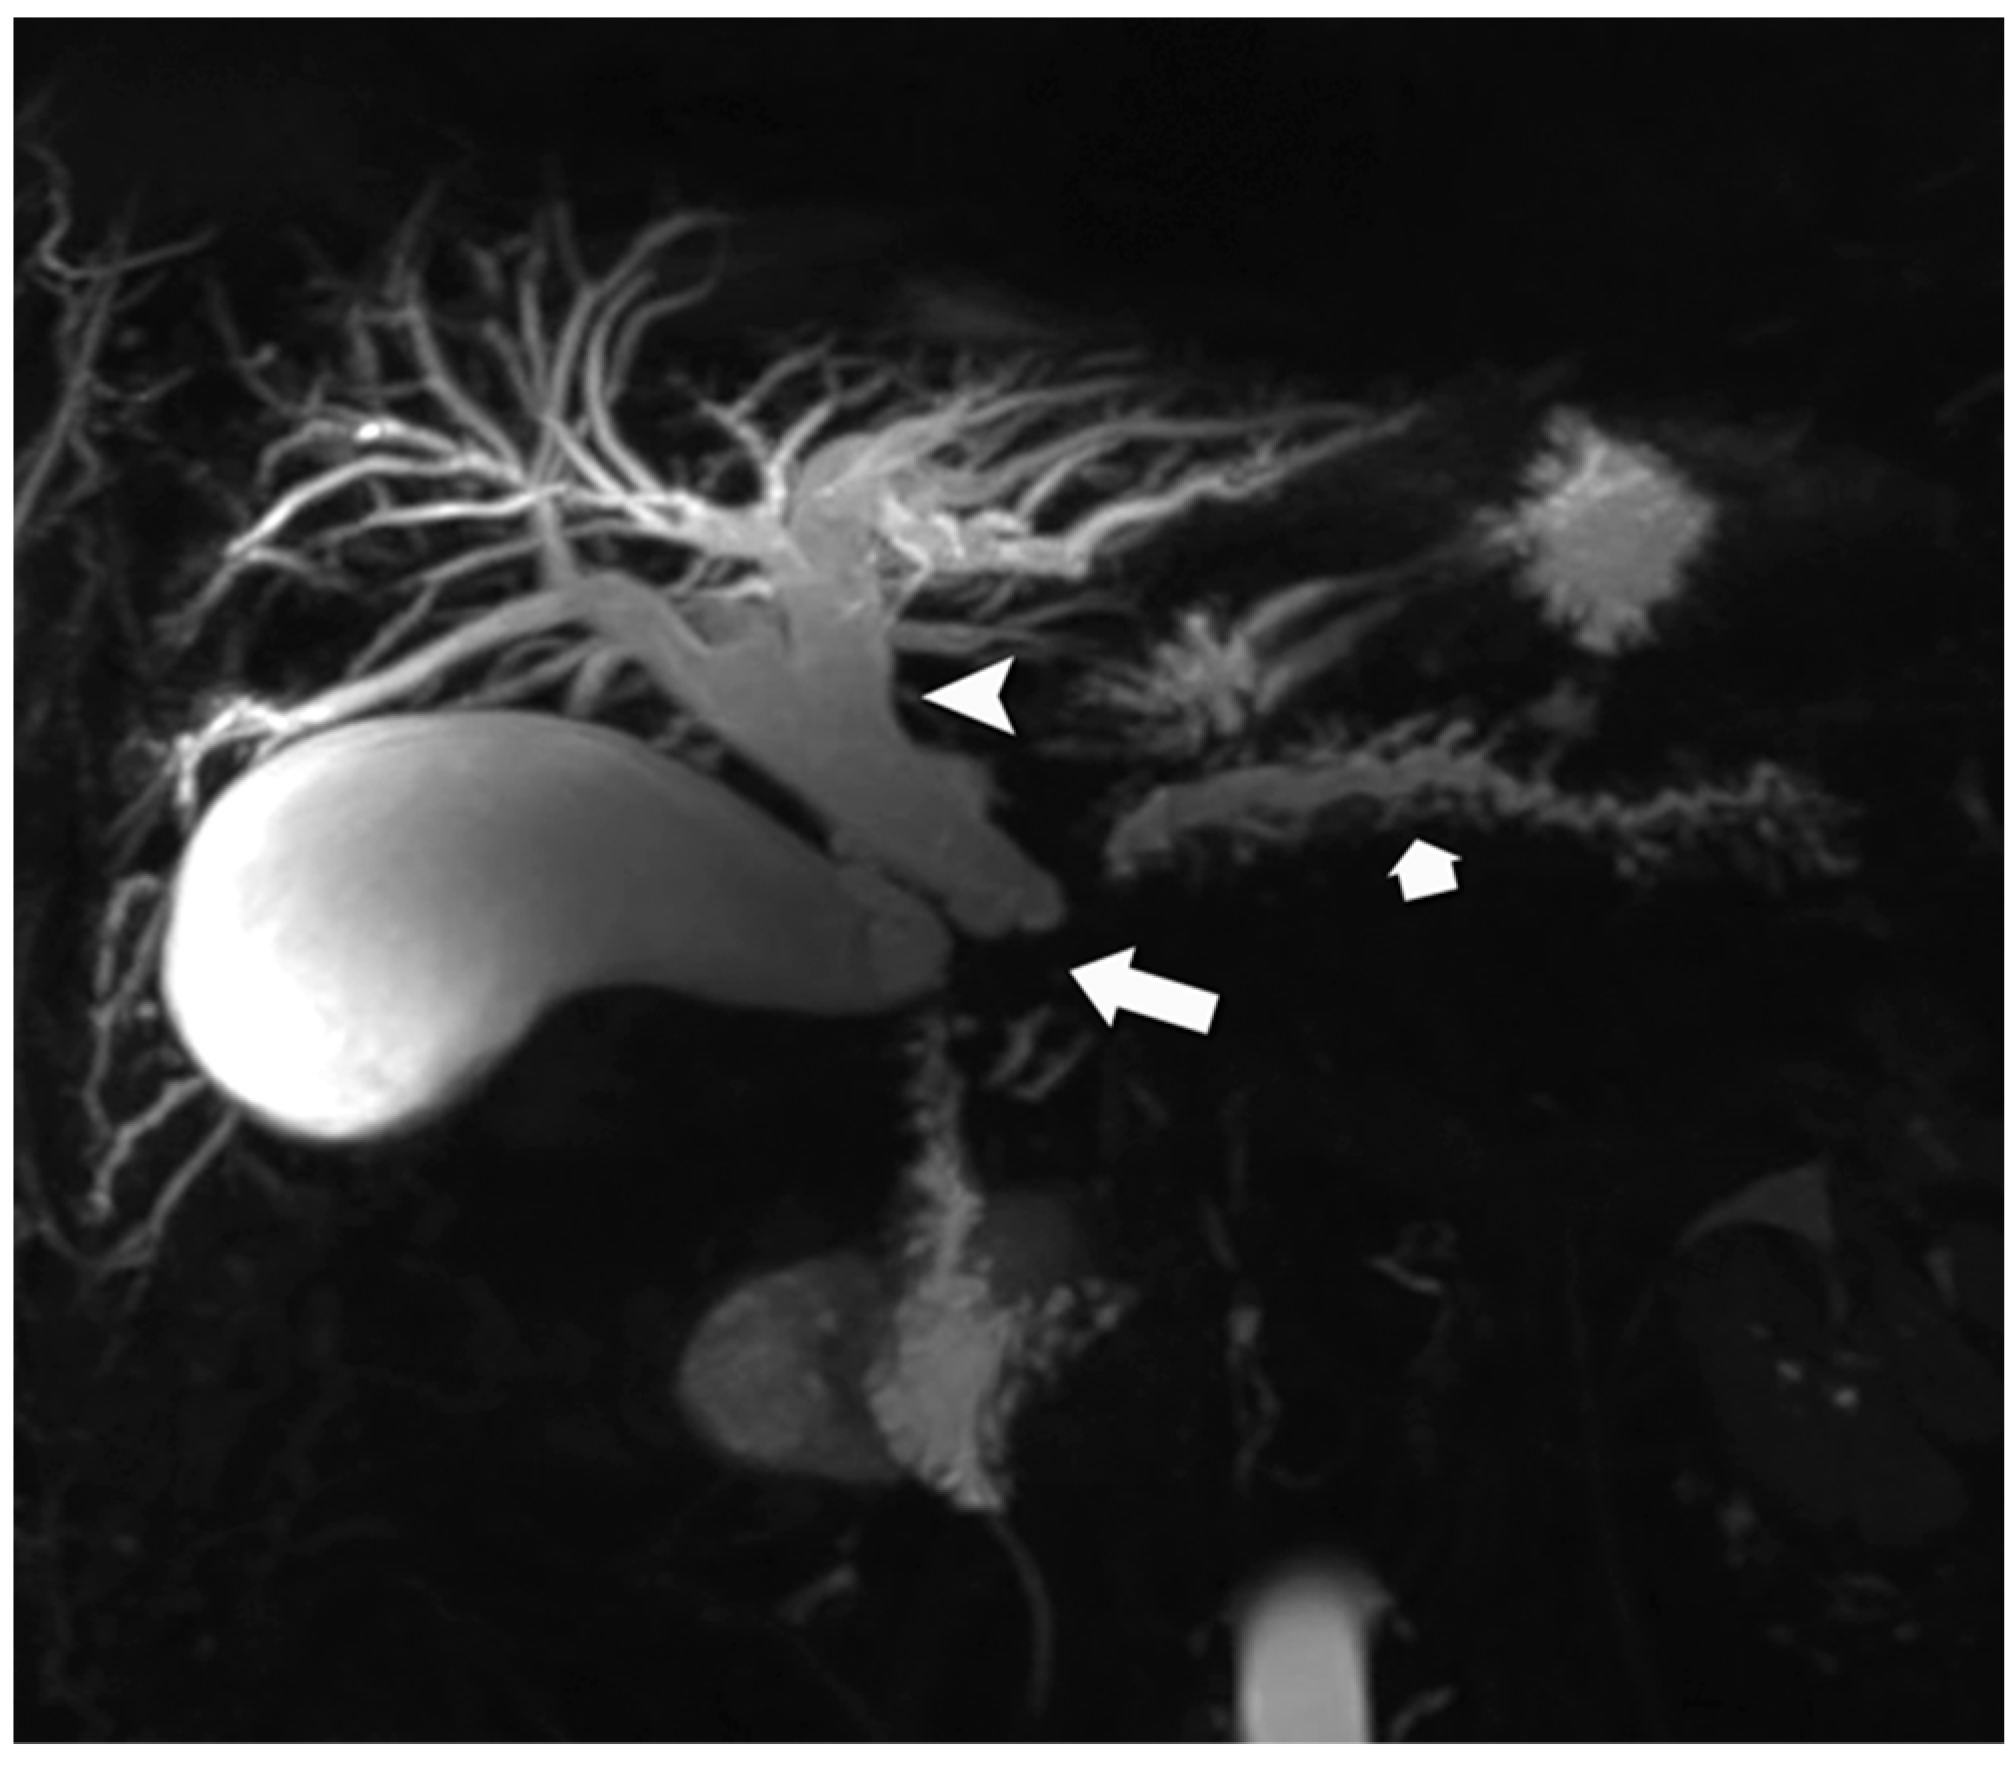

4.1. Morphologic Imaging of NENs